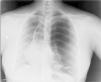

A 31-year-old woman from Pakistan with no significant clinical history consulted due to pleuritic pain of two days duration in the left hemithorax, radiating to the ipsilateral flank with mild hemoptysis. On arrival in the emergency room, she had 38° fever and chills. On auscultation, reduced breath sounds were found on the left side, and accordingly a chest X-ray was performed (Fig. 1, see figure legend).

In view of the radiological image, the chest surgery unit of the reference center was contacted and an angio-CT was performed. This showed voluminous bullae and cystic lesions in the left hemithorax of up to 20cm in diameter, with atelectasis of the pulmonary parenchyma, patent bronchi and air-fluid level in the left pleural space, and left anterior and basal pneumothorax; the right lung showed small subpleural nodules measuring less than 1cm in upper and lower lobes and normal pleural cavity.